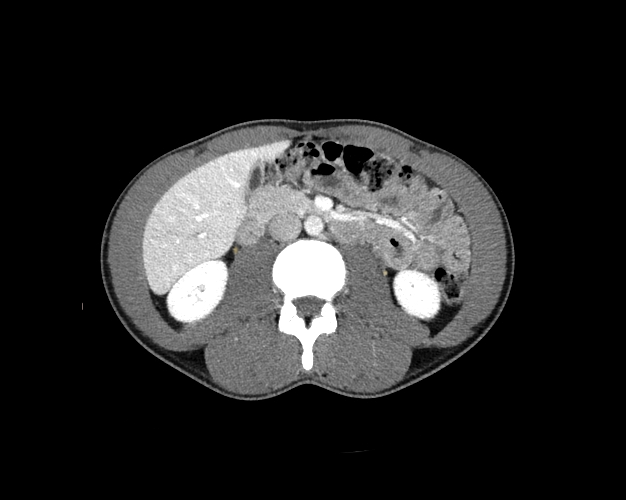

Body

Covers abdominal CT anatomy.